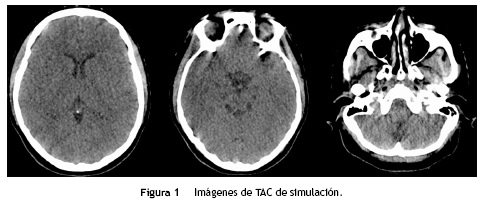

A continuación se presenta una serie de imágenes en las que se compara la calidad de la imagen en la TAC de simulación con la resonancia magnética. Posteriormente, se presentan las imágenes de la fusión realizada y los volúmenes de delimitación. Por último, se muestran las imágenes de dosimetría en las cuales es posible apreciar la diferencia de dosis administrada a las lesiones y a los órganos sanos a riesgo.

En la figura 1 se presentan diversos cortes de la TAC de simulación en donde se observa que las lesiones metastásicas son de difícil visualización y no es posible realizar una correcta identificación de los hipocampos, por lo cual su delimitación no sería ideal.